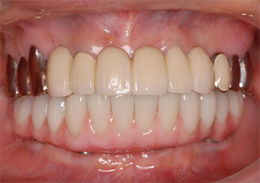

ALL-ON-4(オールオンフォー)の症例写真

上顎のALL-ON-4(ノーベルクリニシャンを使用したフラップレス術式)

- 主訴

- 歯周病で歯がグラグラするので噛めない

- 治療内容

- 上顎に残存していた歯を抜歯。歯肉の治癒後にフラップレス手術にてインプラント埋入を行い、その場で準備してあった上顎上部構造を仮歯として、ねじ固定式で装着

- 治療費用

- 上顎ALL-ON-4:4,000,000円(税別)

- 治療期間

- 6ヶ月